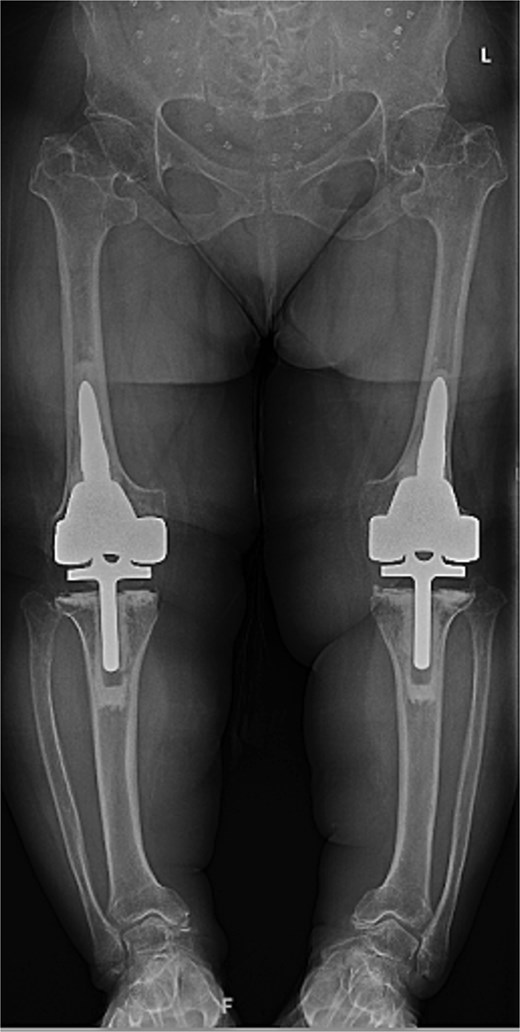

At the 2-year follow-up, the patient reported no significant pain, demonstrated a normal gait, and had active bilateral knee range of motion from 0° to 125°. There was no joint line tenderness or instability. Surveillance radiographs confirmed well-aligned and stable components with no evidence of implant failure or periprosthetic lucency (Fig. 3). At the five-year follow-up, the patient remained very satisfied with her knees and denied knee pain. On exam, her gait was slightly antalgic, but active bilateral knee range of motion remained preserved at 0° to 120°, and both knees remained stable throughout range of motion and nontender to palpation. Radiographs continued to show stable prosthetic components without evidence of implant failure or periprosthetic lucency (Fig. 4).

Five-year postoperative AP radiographs showing continued stability of bilateral rotating-hinge implants with maintained alignment and no radiographic evidence of implant failure.